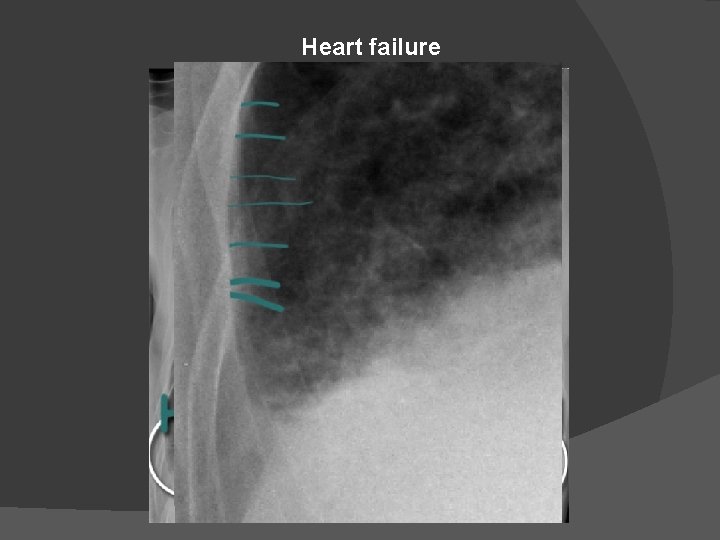

Heart failure